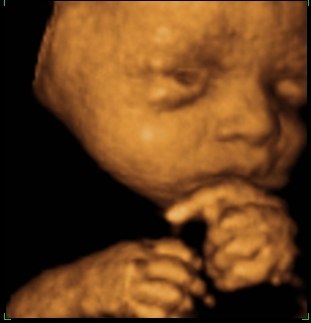

så var vi til 3D scanning i fredags. Så vild en oplevelse.. Hun er bare helt perfekt.

hun vejede 1423g, og så var hun en uge foran så det var da super dejligt at vide at lille pigen har det super og lever luxus derinde i maven

vi var heldige med at hun var rigtig aktiv plus vi også så hende med åbne øjne